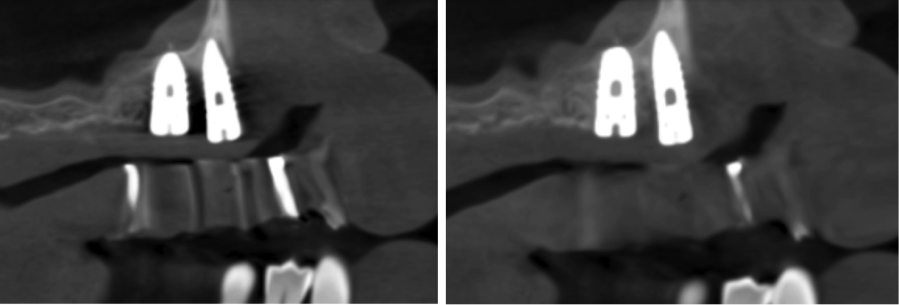

Other kinds of artifacts that are related to the CBCT technology itself may be present and compromise image quality, sometimes rather significantly.7 These artifacts are an inherent problem of CBCT and medical computed tomography because their appearance is a product of the reconstruction algorithms employed to compose the digital CBCT and CT images. In addition, the presence of any radiopaque materials is a frequent cause of artifacts. Metallic dental restorations, fixed prostheses, posts, and even gutta-percha may create artifacts that can obscure the visualization of the region of interest (Figure 3). As a result, fine diagnostic tasks may be impossible in proximity to restorations with high radiopacity. A number of CBCT manufacturers currently offer artifact reduction applications. These seem to have improved the resulting image quality; however, any possible gain in diagnostic efficiency has yet to be determined (Figure 4).

(4.) When compared to the original CBCT image (left), the application of artifact reduc- tion algorithms have improved the visualization between the two dental implants (right image).

Figure 4